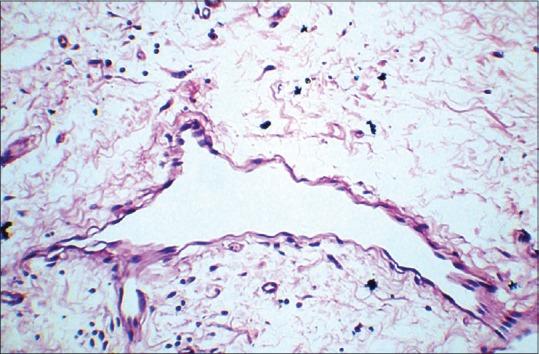

Routray Samapika, Mohanty Neeta, Panda Swagatika, Sahoo Sujit Ranjan

Department of Oral Pathology and Microbiology, Institute of Dental Sciences, Siksha'O' Anusandhan University, Ghatikia, Bhubaneswar, Orissa, India.

J Oral Maxillofac Pathol. 2015 May-Aug;19(2):260-2. doi: 10.4103/0973-029X.164546.